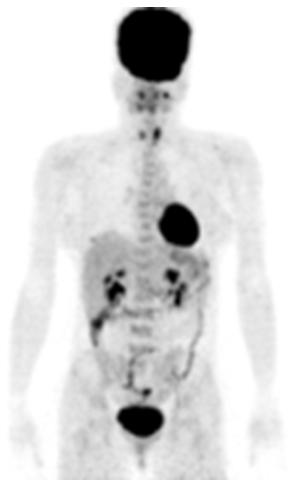

Kết quả chụp PET/CT:

Hình chụp PET/CT toàn thân

Nhân thùy phải tuyến giáp, kích thước: 1,4x1,0cm tăng hấp thu FDG, maxSUV=5,11. Nhân thùy trái tuyến giáp, kích thước: 1,9x1,6cm tăng hấp thu FDG, maxSUV=6,8.

Hình ảnh nốt kích thước: 1,6x1,2cm vị trí 1/4 dưới trong vú phải

tăng hấp thu FDG, max SUV=2,8.

Hình ảnh niêm mạc tử cung tăng hấp thu FDG sinh lý trong chu kỳ kinh nguyệt, SUV=5,4.

Hình ảnh tổ chức thành bụng trước bên phải KT (1,8x1,2)cm tăng hấp thu FDG, max SUV=4,1.

Như vậy các kết quả chụp và xét nghiệm tế bào học cho thấy: Nhân hai thùy tuyến giáp, tổ chức thành bụng trước phải là lành tính, chỉ có khối u vú tăng hấp thu FDG (hướng tới carcinoma) là vấn đề cần chú trọng nhất.